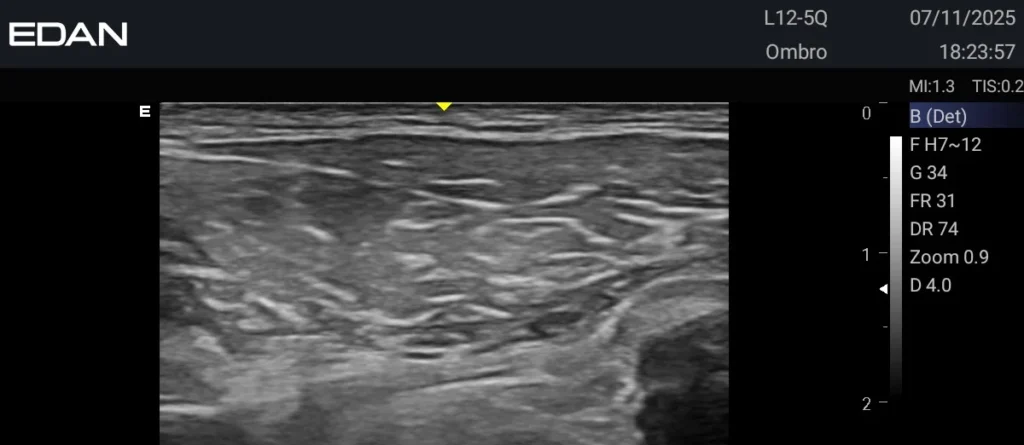

Ultrassom Portátil AX Edan

A linha AX da Edan reúne portabilidade, alta definição de imagem e recursos avançados como Doppler e modo 3D, ideais para exames obstétricos, cardíacos e abdominais. Com design leve, tela sensível ao toque e bateria de longa duração, os modelos oferecem praticidade no dia a dia sem abrir mão da precisão.

O AX3 é o modelo mais avançado da série, com processamento superior para diagnósticos rápidos e confiáveis. Já o AX2, bastante conhecido, ajudou a consolidar a reputação da Edan em ultrassons portáteis de qualidade.